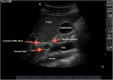

Figures